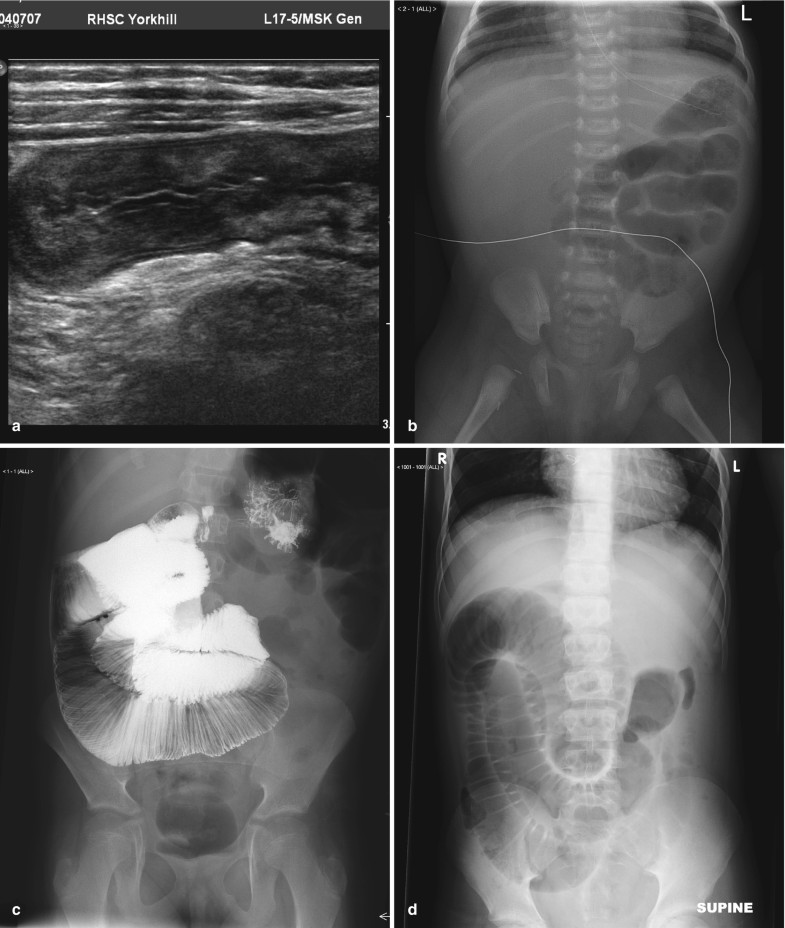

Request a Demo 14 Day Free Trial Buy Now. A non-obstructive bowel gas pattern is now pretty much a defunct Radiologic term which means the findings are not sufficiently specific for bowel obstruction. A physiological stool burden means you have a normal amount of stool in your colonNothing bad. A lack of precision in this report may adversely affect patient care. Your doctor may order this to see what the cause of your abdominal pain or symptoms is. 1 9 10 Nonobstructive bowel dilatation is a rare entity and may be the result of intrauterine fetal compromise congenital chloride diarrhea Hirschsprung disease congenital.

ICD-10-CM Code for Other intestinal obstruction K5669 ICD-10 code K5669 for Other intestinal obstruction is a medical classification as listed by WHO under the range - Diseases of the digestive system. Im only addressing the first question. I suggest you look the article by Dean Maglinte MD titled something like The Non-specific Bowel Gas Pattern. It could be an obstruction or. A non-obstructive bowel gas pattern is now pretty much a defunct Radiologic term which means the findings are not sufficiently specific for bowel obstruction.

ICD-10-CM Diagnosis Code H50042. ICD-10 CPT HCPCS DRG More. The patients with complete hemivaginal obstruction have significantly different presentation when compared to those with. Perhaps there may be a dilated look or air fluid levels but the radiologist is not sure. I suggest you look the article by Dean Maglinte MD titled something like The Non-specific Bowel Gas Pattern.

I suggest you look the article by Dean Maglinte MD titled something like The Non-specific Bowel Gas Pattern. What is a non obstructive bowel gas pattern. Male w Scoliosis There is a mild broad-based dextroscoliosis of the thoracolumbar spine There is a gastrostomy tube in place and a partially obstructive bowel gas pattern. The radiology report is the primary means of communication between the radiologist and the referring physician. Non-Specific Bowel Gas Pattern.

A non-obstructive bowel gas pattern is now pretty much a defunct Radiologic term which means the findings are not sufficiently specific for bowel obstruction. You will see this in the conclusion or the impression of the report of an abdominal X-ray. Legal intervnt w unsp gas law enforc offl injured subs. Male w Scoliosis There is a mild broad-based dextroscoliosis of the thoracolumbar spine There is a gastrostomy tube in place and a partially obstructive bowel gas pattern. The patients with complete hemivaginal obstruction have significantly different presentation when compared to those with.

Idiopathic sleep related non-obstructive alveolar hypoventilation. Request a Demo 14 Day Free Trial Buy Now. R143 is a billablespecific ICD-10-CM code that can be used to indicate a diagnosis for reimbursement purposes. This will fall in between the normal bowel and grossly abnormal blocked bowel. Now getting to the non specific bowel gas pattern.

Request a Demo 14 Day Free Trial Buy Now. Now getting to the non specific bowel gas pattern. ICD-10-CM Diagnosis Code H50042. We examined how radiologists would define nonspecific abdominal gas pattern and how referring physicians would perceive the meaning. Idiopathic sleep related non-obstructive alveolar.

This is the American ICD-10-CM version of R143 - other international versions of ICD-10 R143 may differ. Cases demonstrating single or multiple loops of borderline or slightly dilated small intes- tine 25 cm to 3 cm with 3 or more air-fluid levels on upright or decubitus films. Functional diarrhea K591. Mild small bowel stasis abnormal but nonspecific pattern is defined as those. Non obstructive bowel pattern on abdominal X-ray means no evidence of bowel obstruction normal.